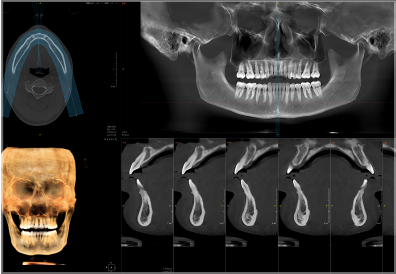

Pirox-A采用多射源并行扫描技术,360°扫描一圈,即可实现非拼接超大视野成像。

实现3D“一成三”成像

单圈扫描可同时获得CT、3D全景及3D正侧位影像,患者无需多次摆位。

视野最大可至24×21cm,即使对于体型偏胖、脸型较大的患者,也都游刃有余。多种视野范围可供临床选择:24×21cm、16×13cm、5×5cm。

24×21的视野,可以完全覆盖患者上至额顶、下至颈角部位,前至鼻尖的范围